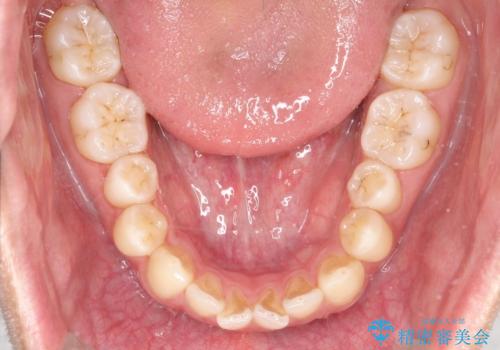

【MSE+インビザライン】前歯のガタガタ

- 前歯の凸凹を主訴に来院されました。

上の歯のアーチが狭窄していたため、骨の幅を広くするためにMSE(急速拡大装置)を使用してからインビザライン にて治療を行いました。

MSE(急速拡大装置)を用いたことで、短期間で奥歯の噛み合わせもしっかりと治すことができました。